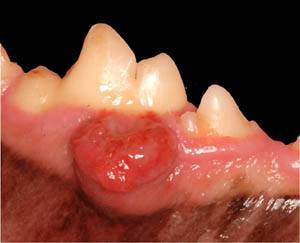

A recent groundbreaking study of clinical, histological and immunological data of 22 cases of Pemphigus foliaceus, or PF, shows evidence that it can occur as an adverse drug reaction to the canine flea and tick preventive ProMeris.

PF is the most common spontaneously occurring autoimmune skin disease of dogs and typically displays as lesions on the face, nasal planum and ears. The reaction is rare but serious, says the study�s lead author, Thierry Olivry, DrVet, PhD, Dipl. ACVD, of North Carolina State University.

The study found that ProMeris Duo-associated PF not only had a reaction to the same drug, but also shared many of the same phenotypes. Lesions in PD-triggered PF were found to be both localized and at distant locations from the point of application.

Skin biopsies from said PD-associated lesions had to reveal microscopic characteristics similar to those of PF, which means the presence of superficial keratinocyte acantholysis.